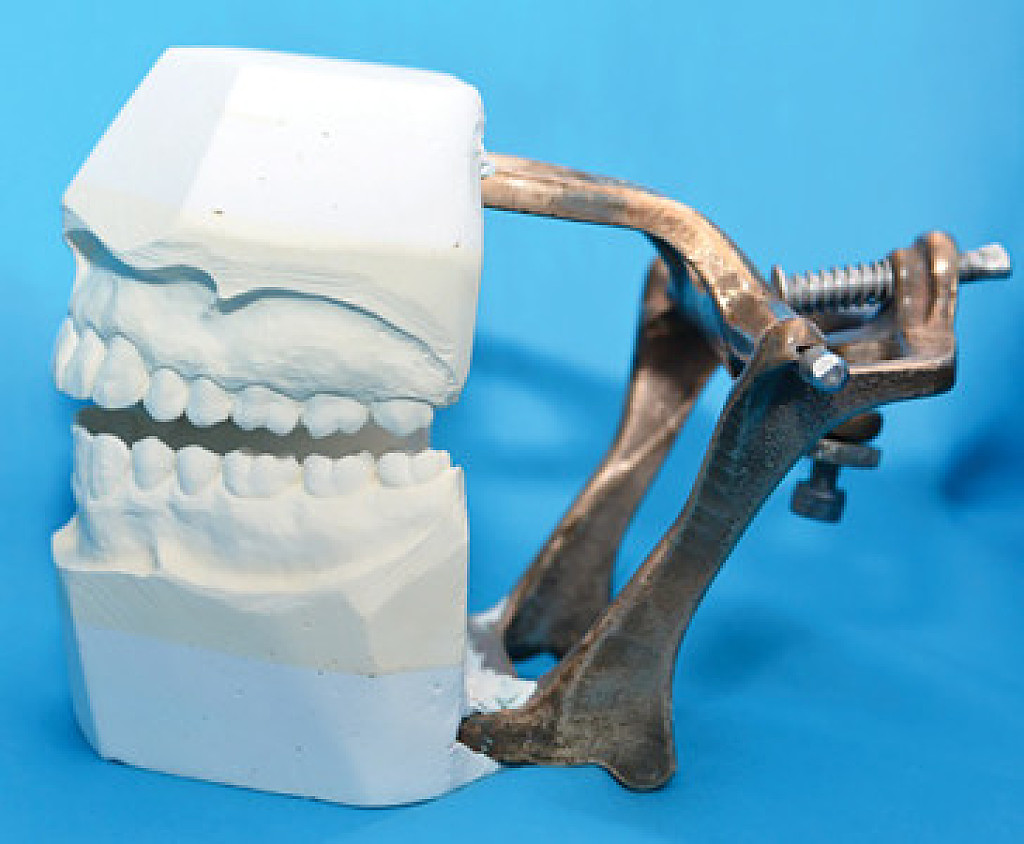

Dentists may precipitate a variety of biomechanical problems with anterior restorations which interfere with anterior guidance. To ensure a predictable outcome it is important either to conserve anterior guidance or reorganise it in a controlled and predictable way. For work involving more than just a couple of indirect restorations access to a facebow and a lab which uses a semi-adjustable articulator is invaluable.